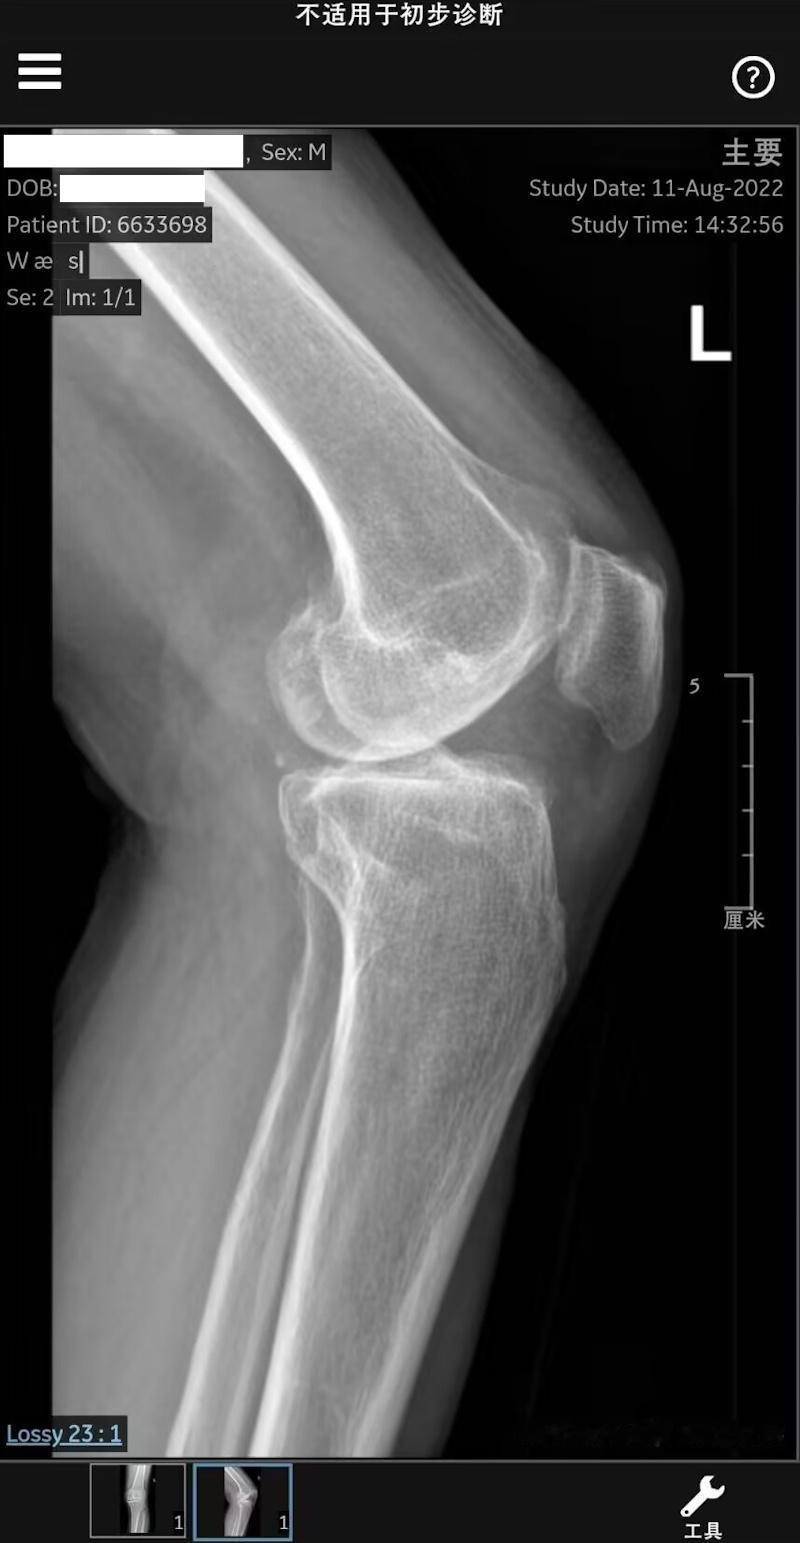

全膝关节置换术后拍的片子,发白的两块就是植入的假体。医生说说保养好的话,能用30

膝关节置换术第8天,目前我们在一家医院做康复。现在主要就是腿还在疼,而且肿和大腿